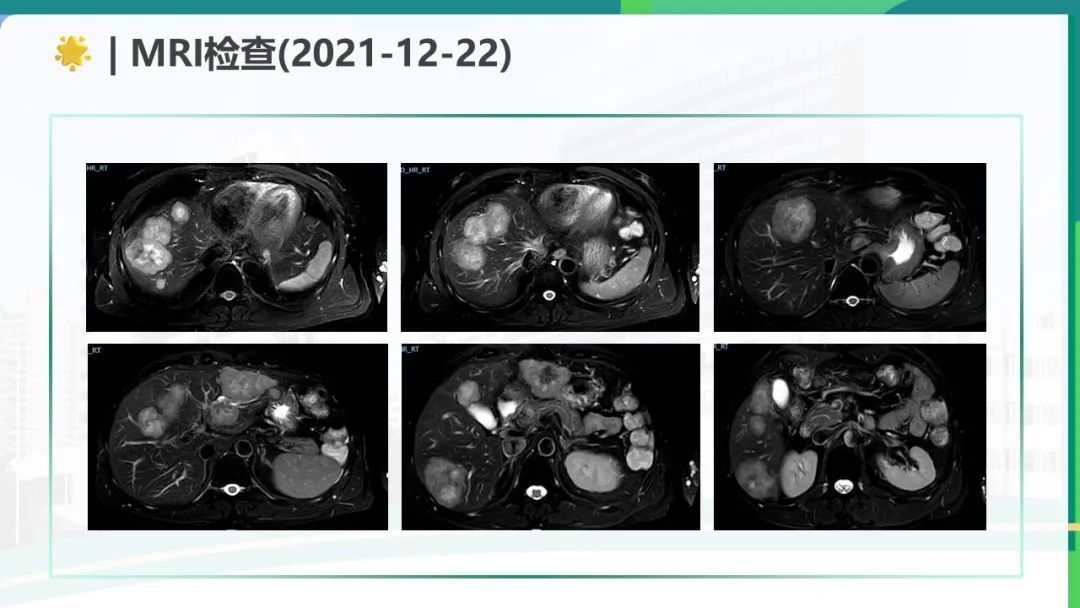

这篇直肠腺癌伴肝转移的MDT病例展示了规范化诊疗流程与多学科协作的重要性,同时也反映了晚期肿瘤治疗的复杂性。1. 初始评估与治疗目标明确性:病例通过肠镜、病理、影像学及基因检测完成了精准分期(cT3cN2M1a IVa期),并基于KRAS突变状态排除了抗EGFR治疗可能。MDT团队在初始不可切除状态下确立了"转化治疗+争取NED"的目标,符合ESMO指南推荐,体现了对治疗预后的科学判断。2. 转化治疗的方案选择与疗效:采用FOLFOXIRI三药化疗联合贝伐珠单抗是高风险结直肠癌转化的标准方案。影像学显示肝转移灶从最大45mm缩小至18mm,直肠壁厚度显著改善,肿瘤标志物CEA从376降至正常范围,证明该方案的高效性。但需注意三药方案的毒性管理(如骨髓抑制、神经毒性)。3. 手术策略的创新性:达芬奇机器人辅助手术实现超低位保肛(距肛门3cm),同时术中超声发现MRI未检出的DLM病灶并完整切除,体现了技术进步对手术精准度的提升。肝转移灶采用"切除+消融"组合策略,符合ESMO对寡转移灶局部治疗的推荐。4. 复发后的全程管理:尽管经历多次进展,团队始终尝试通过更换化疗方案(mFOLFOX6、XELIRI)、局部消融及靶向治疗(呋喹替尼)维持NED状态。二线治疗耐受性差可能提示需要更早引入免疫治疗(如MSI检测阴性后考虑PD-1抑制剂)或参与临床试验。该病例成功的关键在于:规范的MDT决策、积极的转化治疗、精准的手术干预及动态的复发管理,为类似患者提供了有价值的诊疗参考。

该病例中,男,55岁,患者主诉大便性状改变3月余,检查发现肝占位1天。经过一系列的检查,诊断为直肠腺癌并肝转移 cTxN2M1(肝) IV期 RAS野生型 MSS,经过邓权通专家规范治疗,该患者的症状明显改善,疾病的病程也得到了控制。在RAS/BRAF野生型转移性结直肠癌(mCRC)患者中,西妥昔单抗联合FOLFOXIRI(奥沙利铂+伊立替康+氣尿嘧啶)相比单纯化疗方案(如FOLFOX或FOLFIRI),可显著延长无进展生存期(PFS)和总生存期(OS)。肝转移转化治疗:中国FOCULM研究证实,改良FOLFOXIRI联合西妥昔单抗可将RAS/BRAF野生型结直肠癌肝转移患者的无疾病证据(NED)转化率显著提高,为初始不可切除患者创造手术机会。